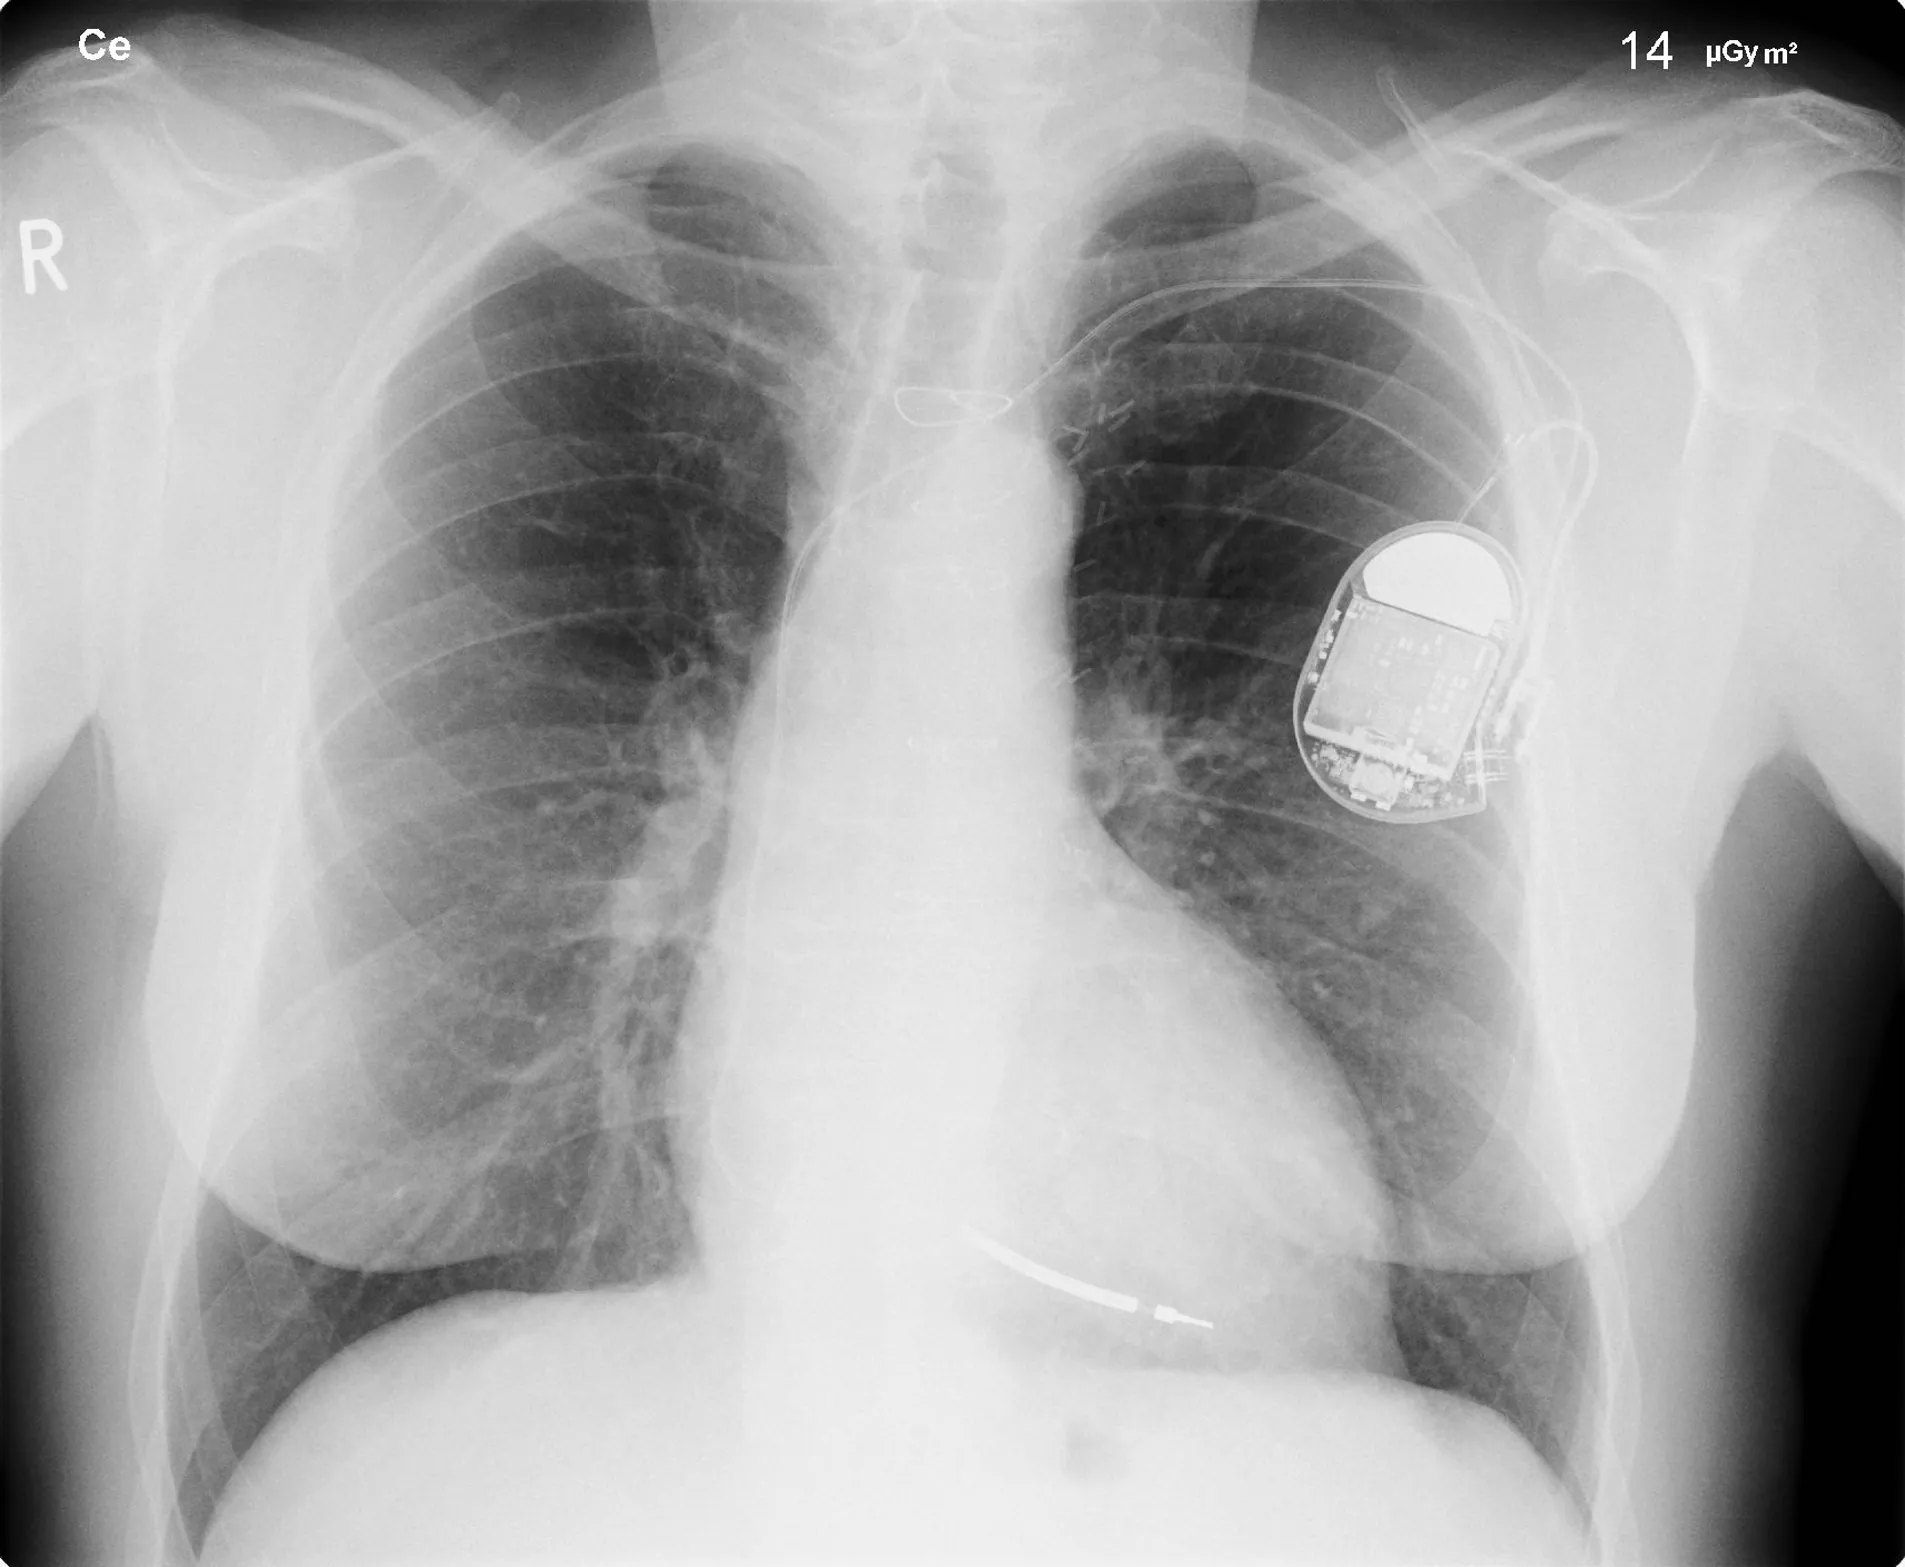

An X-ray image of a person’s chest is shown, clearly showing a pacemaker in the left side.

Figure 30.23 This x-ray image of a person’s chest shows many details, including an artificial pacemaker. (credit: Sunzi99, Wikimedia Commons)

The most common x-ray images are simple shadows. Since x-ray photons have high energies, they penetrate materials that are opaque to visible light. The more energy an x-ray photon has, the more material it will penetrate. So an x-ray tube may be operated at 50.0 kV for a chest x ray, whereas it may need to be operated at 100 kV to examine a broken leg in a cast. The depth of penetration is related to the density of the material as well as to the energy of the photon. The denser the material, the fewer x-ray photons get through and the darker the shadow. Thus x rays excel at detecting breaks in bones and in imaging other physiological structures, such as some tumors, that differ in density from surrounding material. Because of their high photon energy, x rays produce significant ionization in materials and damage cells in biological organisms. Modern uses minimize exposure to the patient and eliminate exposure to others. Biological effects of x rays will be explored in the next chapter along with other types of ionizing radiation such as those produced by nuclei.